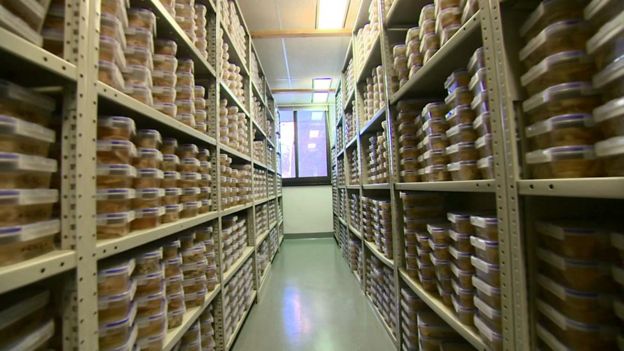

En el Centro de Tejidos Cerebrales Harvard, en las afueras de Boston, hay más de 3000 cerebros almacenados.

En el Centro de Tejidos Cerebrales Harvard, en el Hospital McLean, en las afueras de Boston, Estados Unidos, hay más de 3.000 cerebros almacenados.

Es uno de los bancos de cerebros más grandes del mundo.

La mayoría de los ejemplares son de personas que han sufrido enfermedades mentales o psicológicas.

Los científicos requieren estas muestras para buscar nuevos tratamientos contra el Parkinson o el Alzheimer y para toda una serie de desórdenes psiquiátricos.

Pero las que hay en el centro, así como en otras instituciones en el mundo, no son suficientes y esto está frenando el avance en la investigación.

Según Kerry Ressler, principal jefe de científicos del Hospital McLean, los investigadores tienen las herramientas y la capacidad para hacer estudios del cerebro en gran profundidad, "pero lo que nos faltan son los tejidos de aquellos que padecieron estos desórdenes que nosotros tenemos que comprender cabalmente".